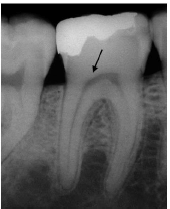

A polpa reage de maneiras diferentes à presença de agentes ou estímulos agressores, e seus principais mecanismos de defesa são: redução da permeabilidade dentinária, formação de dentina terciária e desenvolvimento de uma resposta imune. A partir dos seus conhecimentos sobre radiologia e respostas da polpa à agressão, analise a imagem abaixo e assinale a alternativa que apresenta a descrição correta da representação:

Machado, Ricardo. Endodontia: Princípios Biológicos e Técnicos. Disponível em: Minha Biblioteca, Grupo GEN, 2022.